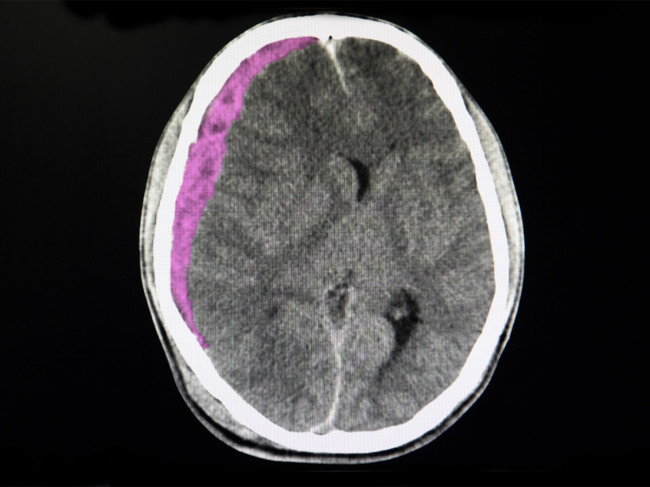

CT scan of brain showing subdural hematoma

Borvo Medical wins 510(k) clearance for SDH drainage device

Borvo Medical Inc., a neurointerventional med-tech startup, reported U.S. FDA 510(k) clearance of its Endoport Vacuum Assisted Collection (EVAC) system, an alternative to traditional subdural hematoma (SDH) drainage methods. The EVAC system is expected to be available in early 2025 the company said. Read More